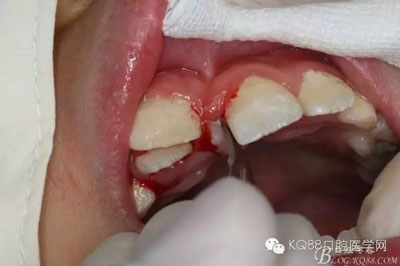

圖1.術前的患者口內(nèi)照片:11與12完全唇腭向重疊,11與21之間有3mm間隙